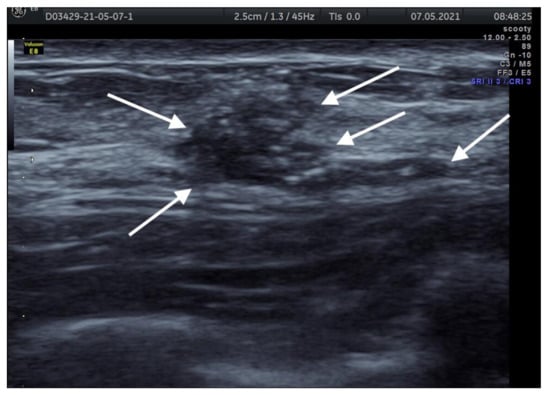

5. Clinical Picture, Diagnostic Criteria

6. Imaging Findings